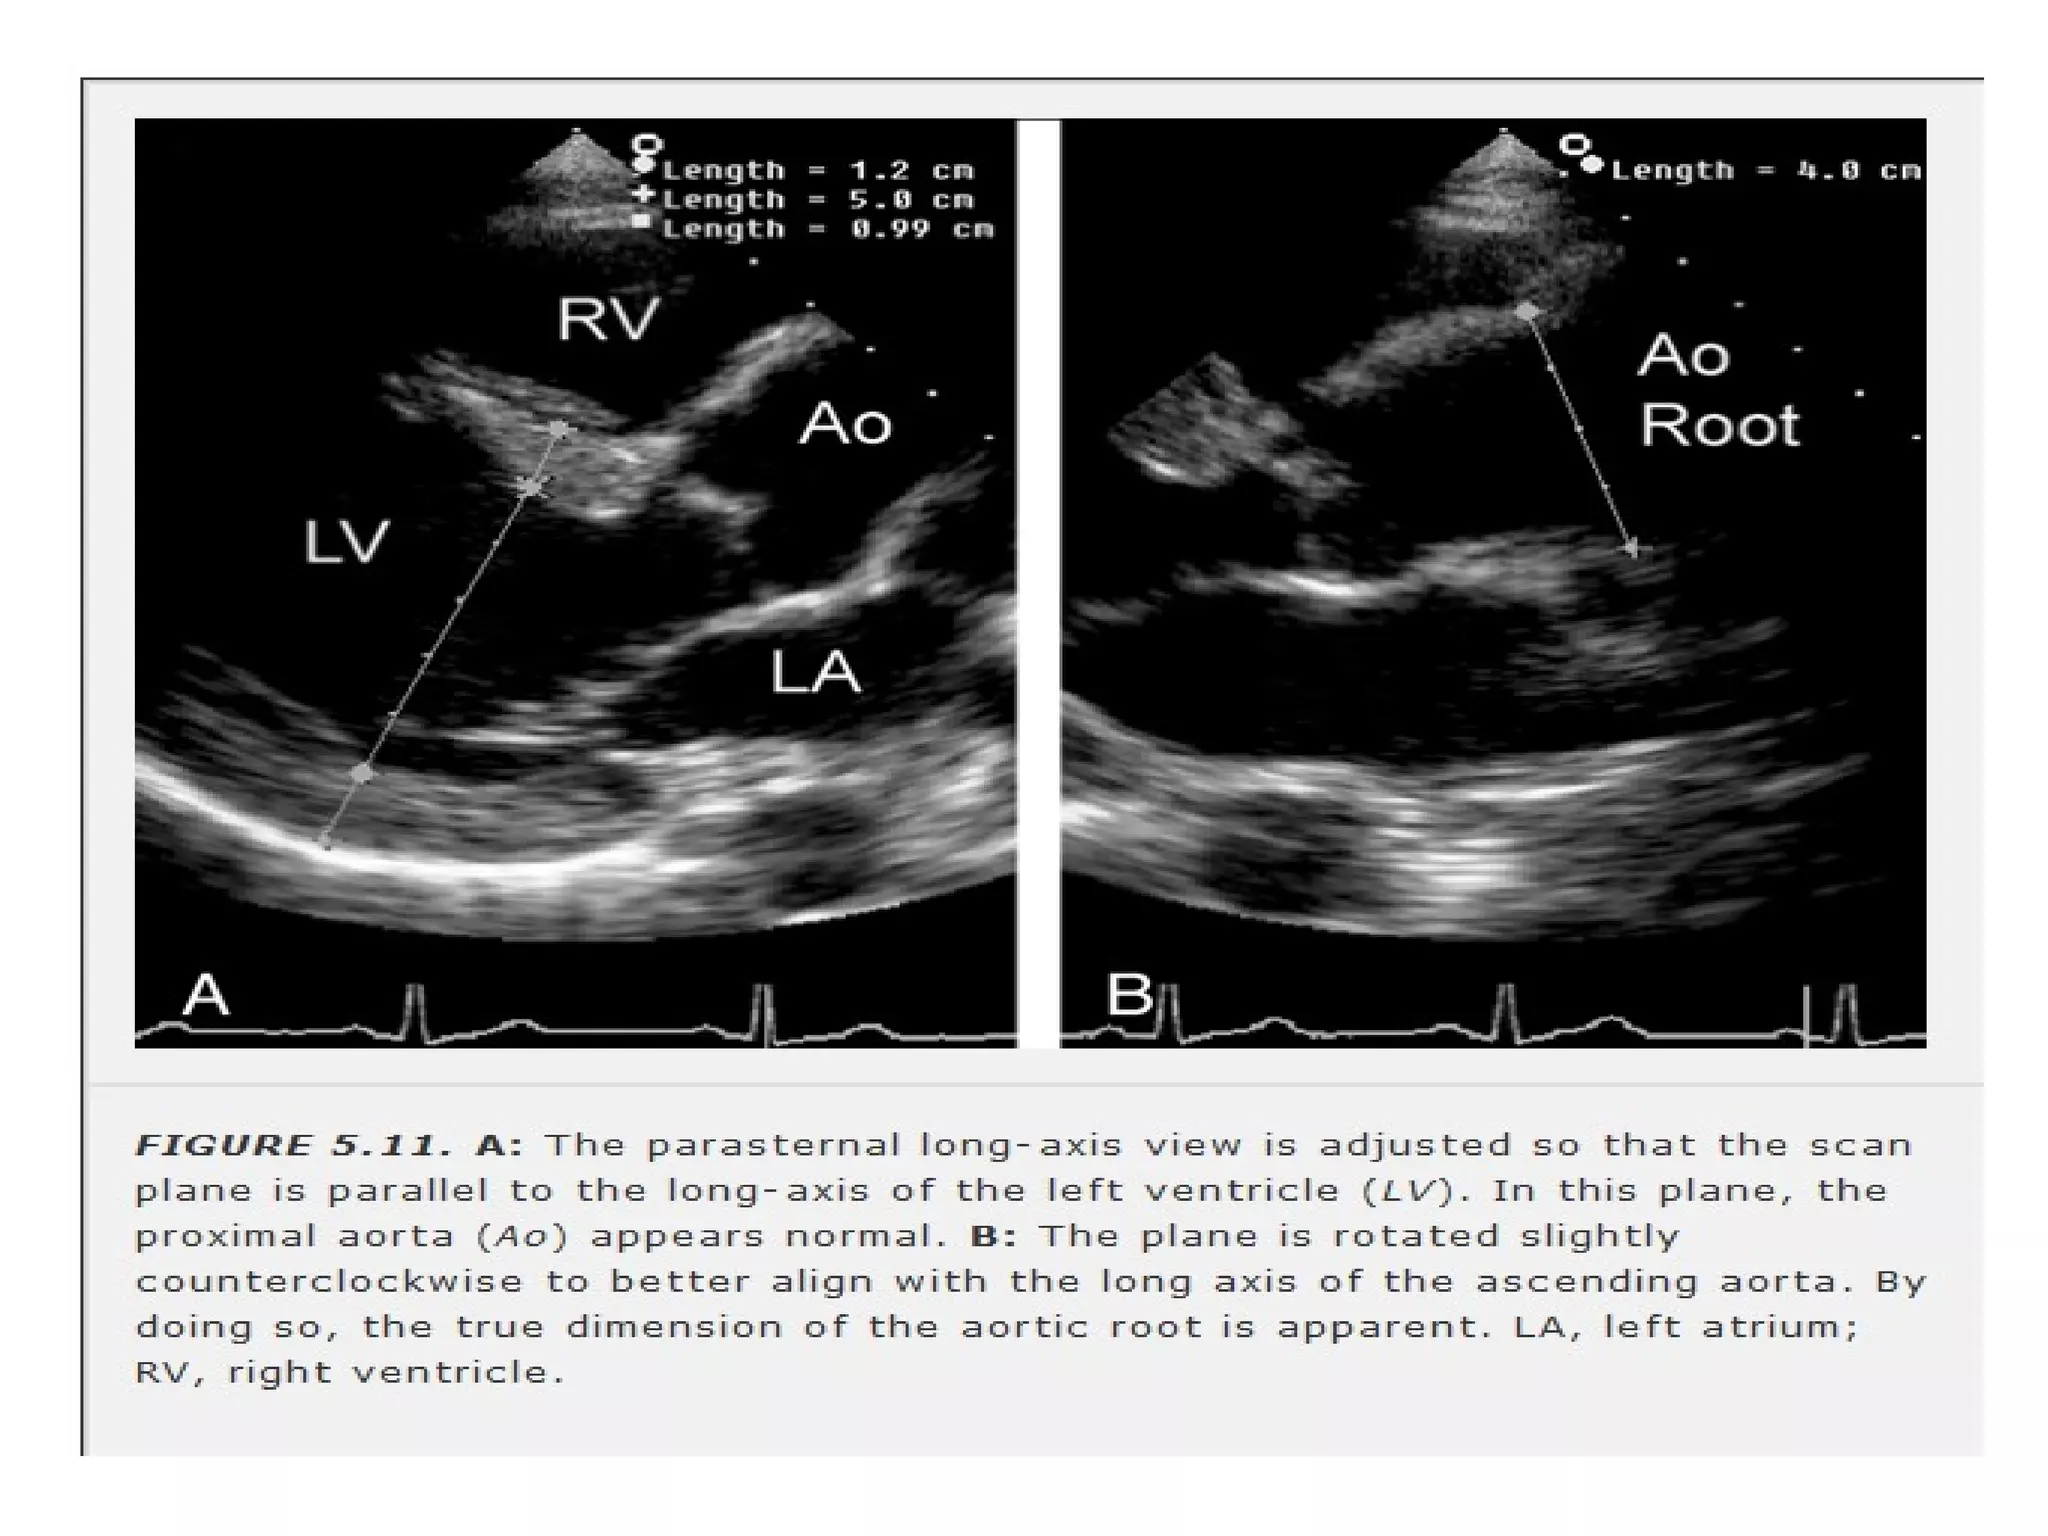

• Mid portion & base of lv ,both leaflets of

MV ,AV ,AO root ,LA &RV.

• imaging plane is aligned parallel to long

axis of lv.

• AORTA

annulus : 1.4- 2.6 cm

at leaflet tips: 2.2- 3.6

asc aorta : 2.1- 3.4

LA

PLAX : 2.3- 4.5